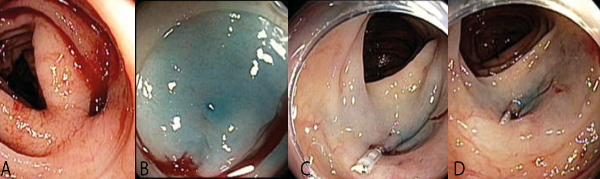

Se logró identificar a nivel de colon transverso proximal sangrado rezumante, de uno de los divertículos que no cedió a la infiltración de adrenalina 6cc. A una dilución de 1:10.000 U. Se procedió a marcar el área peridiverticular y contralateral con inyeccion submucosa de azul de metileno y solución fisiológica y posteriormente se ingresa con capuchon. Se procedió a aplicar dos hemoclips recargables (EZ Olympus). no logrando hemostasia satisfactoria se decide irrigar el fondo diverticular ácido tranexámico 500mg diluido en 20 c.c. de sol fisiológica. a través del canal auxiliar de agua del colonoscopio Olympus CF 180. Cohibiendo el sangrado. Posteriormente se aplicó otros 6 c.c. de adrenalina dil 1:10.000. ( Figura 3) ( Ver video.)

En el presente caso se logró la hemostasia combinando metodos de inyeccion, clips y la irrigación topica de ácido tranexamico. La cual tuvo un efecto adyuvante beneficioso. Como se ve en el video.